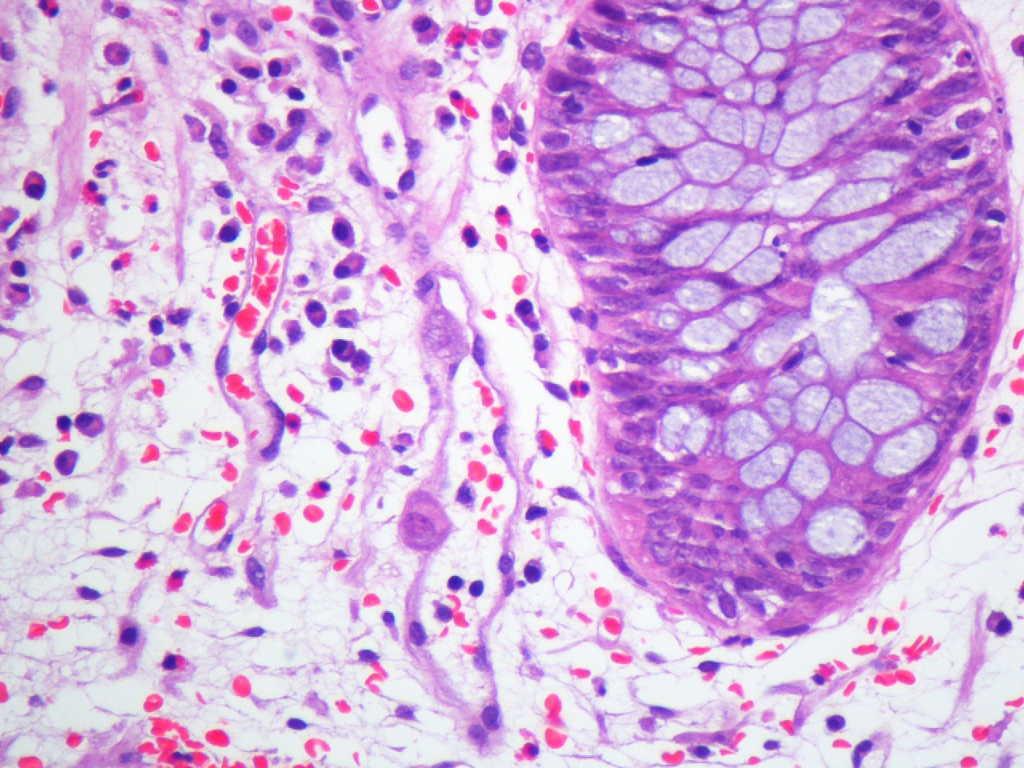

Varón de 60 años con hipertensión arterial esencial, valvuloplastia biológica aórtica y enfermedad renal crónica estadio V de etiología no filiada, en programa de hemodiálisis durante un año. Serología del virus de la hepatitis B (VHB), virus de la hepatitis C (VHC) y virus de la inmunodeficiencia humana (VIH) negativa. IgG CMV positiva. Recibió trasplante renal de donante cadáver. La inmunosupresión se efectuó con tacrolimus, micofenolato mofetilo y prednisona. El paciente presentó un curso clínico sin complicaciones y alcanzó función renal normal. Cuatro años después fue admitido en el hospital por un cuadro diarreico inespecífico no acompañado de otra sintomatología, con coprocultivo negativo, que se resolvió con tratamiento sintomático. Un año después ingresó por el mismo motivo y tras la suspensión de micofenolato mofetilo presentó mejoría clínica con resolución del cuadro, siendo remitido a consultas de digestivo de forma ambulatoria para estudio de diarrea crónica. A los tres meses del ingreso hospitalario se realizó colonoscopia con toma de biopsia, donde se observaron inclusiones citoplasmáticas y nucleares atribuibles a CMV (figura 1) con reacción en cadena de la polimerasa (PCR)-CMV 475 532 copias/ml. La PCR para CMV en plasma era negativa. Recibió tratamiento con ganciclovir intravenoso durante tres semanas. El paciente mantuvo función renal estable durante todo el proceso y permanece asintomático hasta el momento actual, diez meses después del diagnóstico.

Figura 1. Inclusiones citoplasmáticas por citomegalovirus en mucosa intestinal.